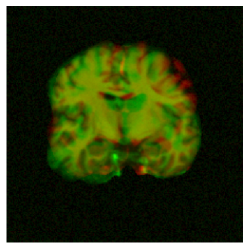

To motivate our work, consider the example in Fig. 1, in which we performed a 3D registration of two MRI brain scans from the OASIS [7] dataset using the popular Stationary Velocity Field (SVF) approach [8, 9, 10] and our proposed method (denoted ). In the first example, the sought deformation is comparably small before the registration process, and both approaches perform equally well. In the second example, the deformation includes a larger rotational component. When looking at the deformed images only, the SVF approach appears to generate an alignment that is clearly worse, but not catastrophically so. This is deceptive: inspecting the generated deformation fields (Fig. 2), it becomes clear that the SVF approach generates a deformation that – while it maps corresponding intensity values reasonably well between the images – is far from the ground truth.

The findings on these (synthetic) examples are compatible with our perception of the existing literature: In general, we found that SVF-based approaches mostly seem to be applied to pre-aligned images, and/or that the judgement of their accuracy is solely based on the similarity of the images after registration or on related proxies, such as the overlap of known segmented regions, that do not necessarily imply sensible deformation fields.

This behavior is clearly visible in Fig. 1 and Fig. 2 shown in the introduction, in which the resultant images as well as an exemplary slice of the deformation field are depicted under small and large deformations. It illustrates how the matrix group approach is able to capture even large rotational deformations, whereas the use of an SVF tends to align the intensity values by local deformations instead of a global rotation, resulting in the large RMSE observed in Fig. 12.